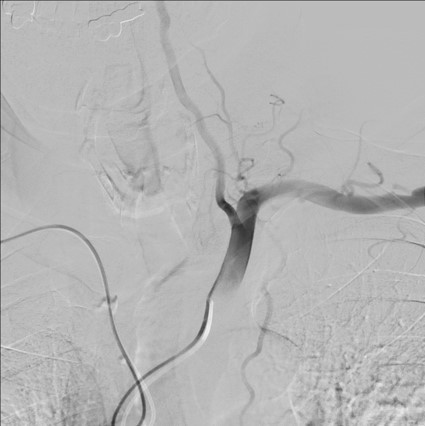

导管超选择左颈动脉